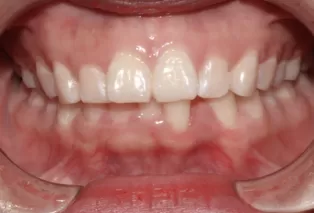

Femme, 25 ans. Plainte principale: dents saillantes et mal alignées, nécessitant un traitement orthodontique.

Avant le traitement

Photos intra-orales